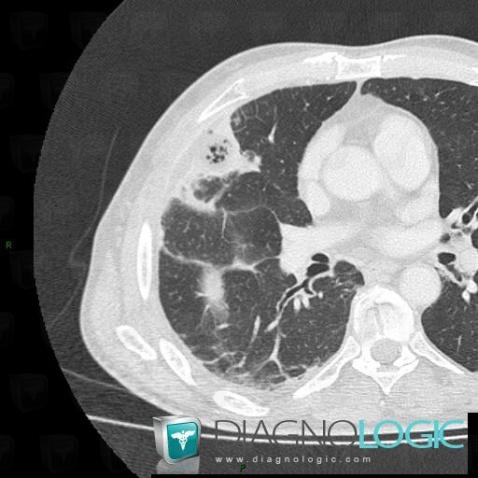

Abscess, Pulmonary parenchyma, CT

Here is the specific information in the key image above:

- Diagnosis Abscess, Location(s) Pulmonary parenchyma, with gamuts Solitary pulmonary nodule, Cavitary pulmonary nodule